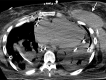

As lung transplantation has become the most effective definitive treatment option for end-stage chronic respiratory diseases, yearly rates of this surgery have been steadily increasing. Despite improvement in surgical techniques and medical management of transplant recipients, complications from lung transplantation are a major cause of morbidity and mortality. Some of these complications can be classified on the basis of the time they typically occur after lung transplantation, while others may occur at any time. Imaging studies, in conjunction with clinical and laboratory evaluation, are key components in diagnosing and monitoring these conditions. Therefore, radiologists play a critical role in recognizing and communicating findings suggestive of lung transplantation complications. A description of imaging features of the most common lung transplantation complications, including surgical, medical, immunologic, and infectious complications, as well as an update on their management, will be reviewed here. Keywords: Pulmonary, Thorax, Surgery, Transplantation Supplemental material is available for this article. © RSNA, 2021.